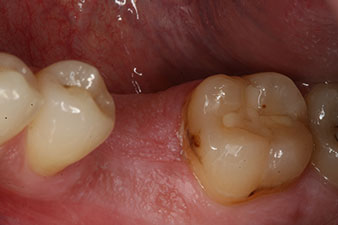

composite crown

Fig. 9: The final composite crown was cemented on a PEEK hybrid abutment in the laboratory and can be screwed in place immediately.

The final pictures show the screw-retained monolithic composite crown in place and the x-ray check (Fig. 9 and 10) (6).